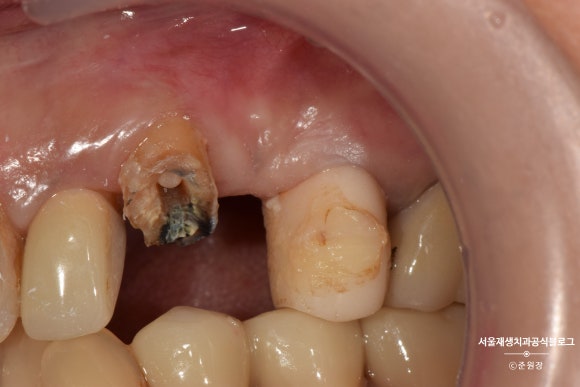

이미 신경치료가 잘 되어 있던 치아라서,

혹시 모를 재감염을 방지하기 위해

뿌리 끝을 약간 잘라냈습니다.

충분한 높이가 확보되었는지 확인하기 위한 치주탐침검사입니다. 눈금이 있어서 '자'처럼 쓸 수 있는 유용한 도구입니다^^

크라운을 씌우기 위해서는 최소 2~3mm의 높이가 필요합니다.